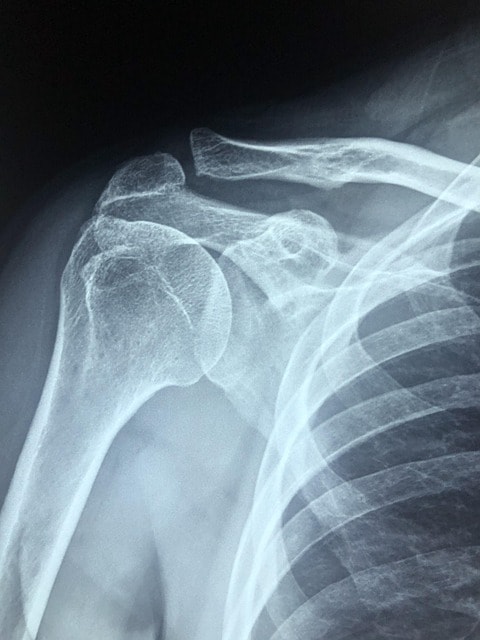

Diagnos och undersökning

Diagnos av kalkaxel baseras på fysisk undersökning och bilddiagnostik som röntgen, ultraljud eller MRI, vilka visar kalkavlagringar och inflammation i axelns senor. Ultraljud kan dessutom visa senförtjockning och blodflöde runt kalkutfällningen, vilket hjälper till att bedöma tillståndets form och stadium.